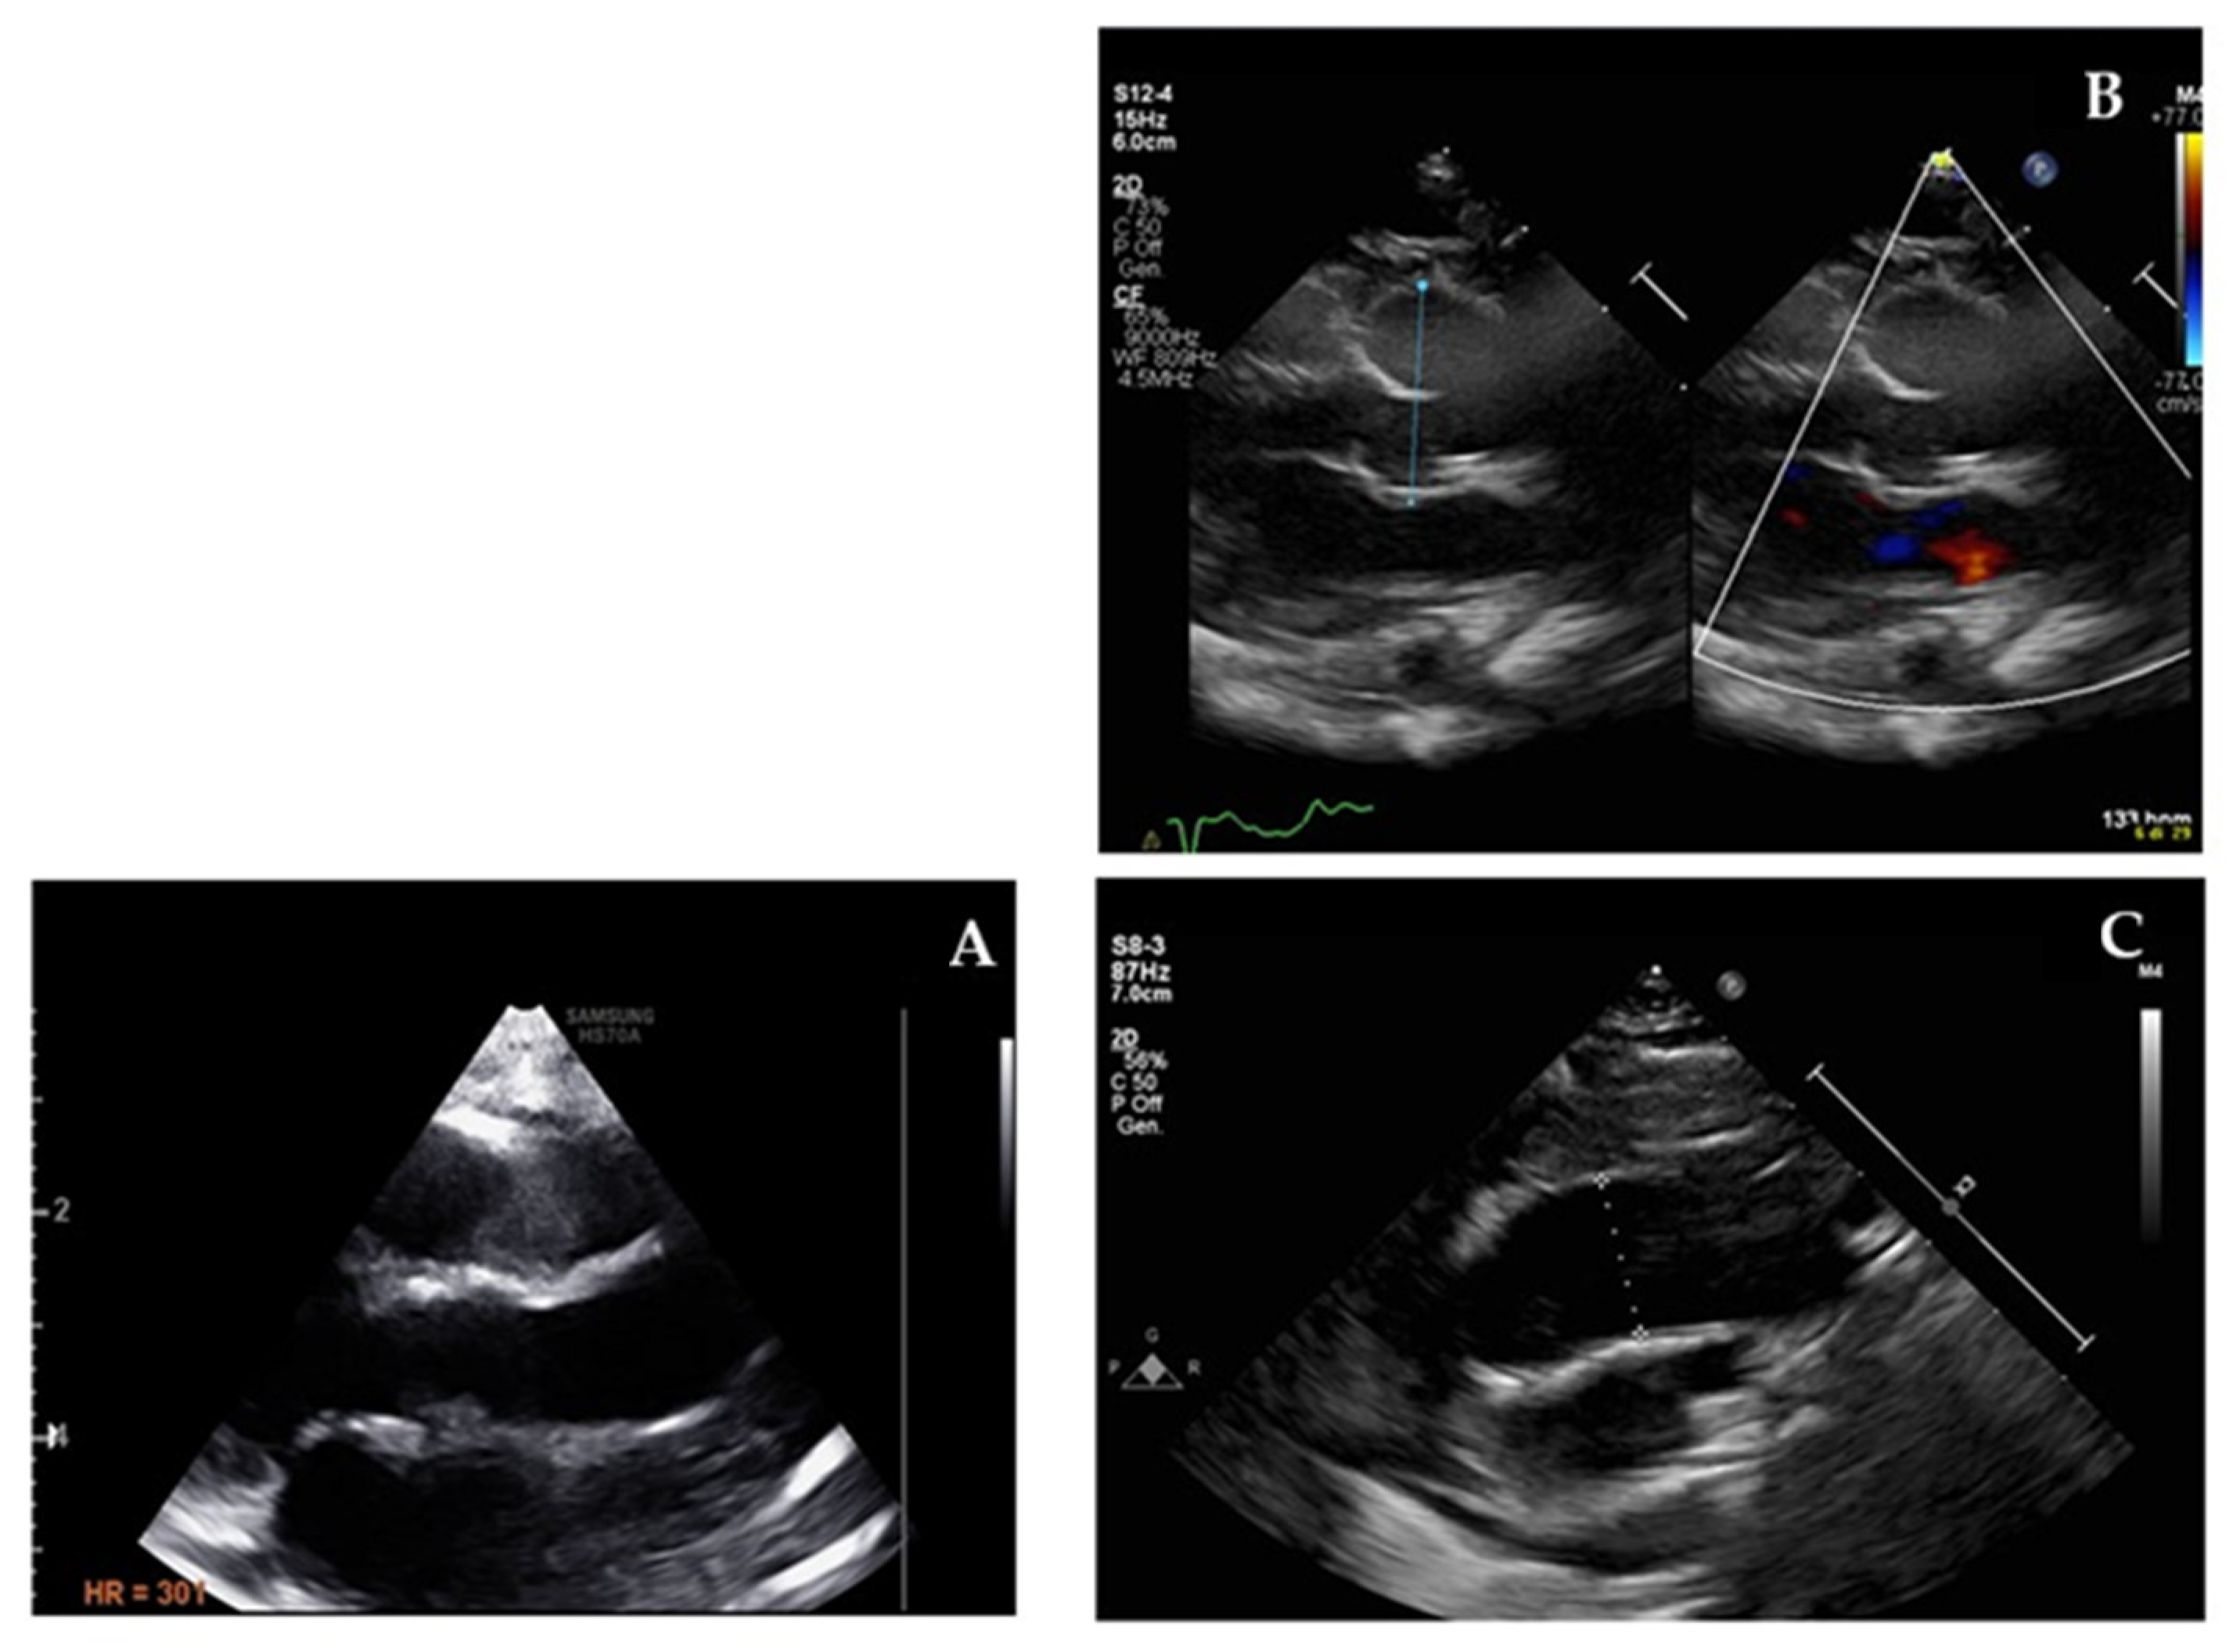

| CHD | ASD | HLHS, Mitro-aortic hypoplasia, VSD, CoAo | Ebstein anomaly with TR, Mild MR and TR | No | ASD | ASD, VSD, PDA surgically repaired | No | No | ASD-OP, mild TR |

| CMP / NCLV | NCLV, EF 45% | No | NCLV, EF 50% | No, EF 67% | NCLV, severe DCMP EF 15% | NCLV, EF 65% | No | Mild LVH | NCLV, EF 45%, mild LVH |

| Aortic dilatation | Normal | Normal | Normal | Normal | Normal | Dilated aortic root, (Z-score 5), and ascending aorta (Z-score 2.9) In losartan therapy | Normal | Dilated aortic root (Z-score 2.5) and ascending tract with mild AR. Lost in F-UP | Dilated ascending aorta (Z-score 2.1); in ACEI and beta-blocker therapy |